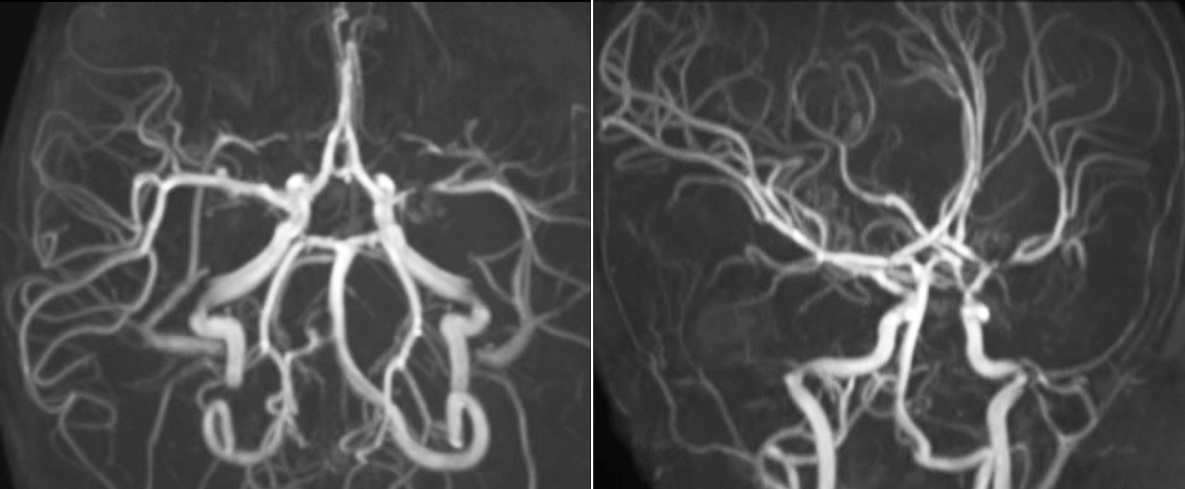

Phoenix Children’s Hospital (PCH, Phoenix, Arizona, USA) is the primary referral children’s hospital for the state of Arizona, serving patients with the most complicated cases. The hospital is using two Ingenia 3.0T systems and two 1.5T systems. “We’re a referral center for complex diseases affecting neurological systems, especially traumatic brain injury, brain tumors, epilepsy, and vascular diseases including stoke,” says PCH neuroradiologist Jeffrey H. Miller, MD. Along with Lead MRI Technologist Amber Pokorney, Dr. Miller utilizes advanced MRI techniques in some of the hospital’s most challenging imaging cases.

SWIp supports diagnostic confidence in traumatic brain injury

The value of susceptibility weighted imaging in visualizing brain injury is well documented. The Philips multi-echo SWIp technique provides fast susceptibility weighted imaging with enhanced susceptibility contrast and high resolution.

“I would definitely recommend other users to implement SWIp. We initially added the SWIp sequence following a lot of support for its utility in the literature. Then we directly compared SWIp to the 2D gradient echo sequences that we were using. After a good amount of clinical experience in seeing its benefits, we were confident to replace the old sequences with SWIp. It gives us a better assessment of the physiological processes of the brain that were less apparent on our previous imaging sequences,” says Dr. Miller. “SWIp is now a routine sequence for imaging traumatic brain injury patients at PCH, and it’s episodically added for patients who have intracranial vascular abnormalities.”

“I believe SWIp is rapidly becoming the standard in imaging traumatic brain injury, because of its high sensitivity to venous blood products. SWIp may even help attract patients; our neurosurgeons often ask to have the patients imaged on our scanners with highly sensitive techniques like SWIp. There’s also a growing application of SWI sequences in other vascular abnormalities because of the possibilities around physiological assessment of the brain than just a standard structural imaging.”